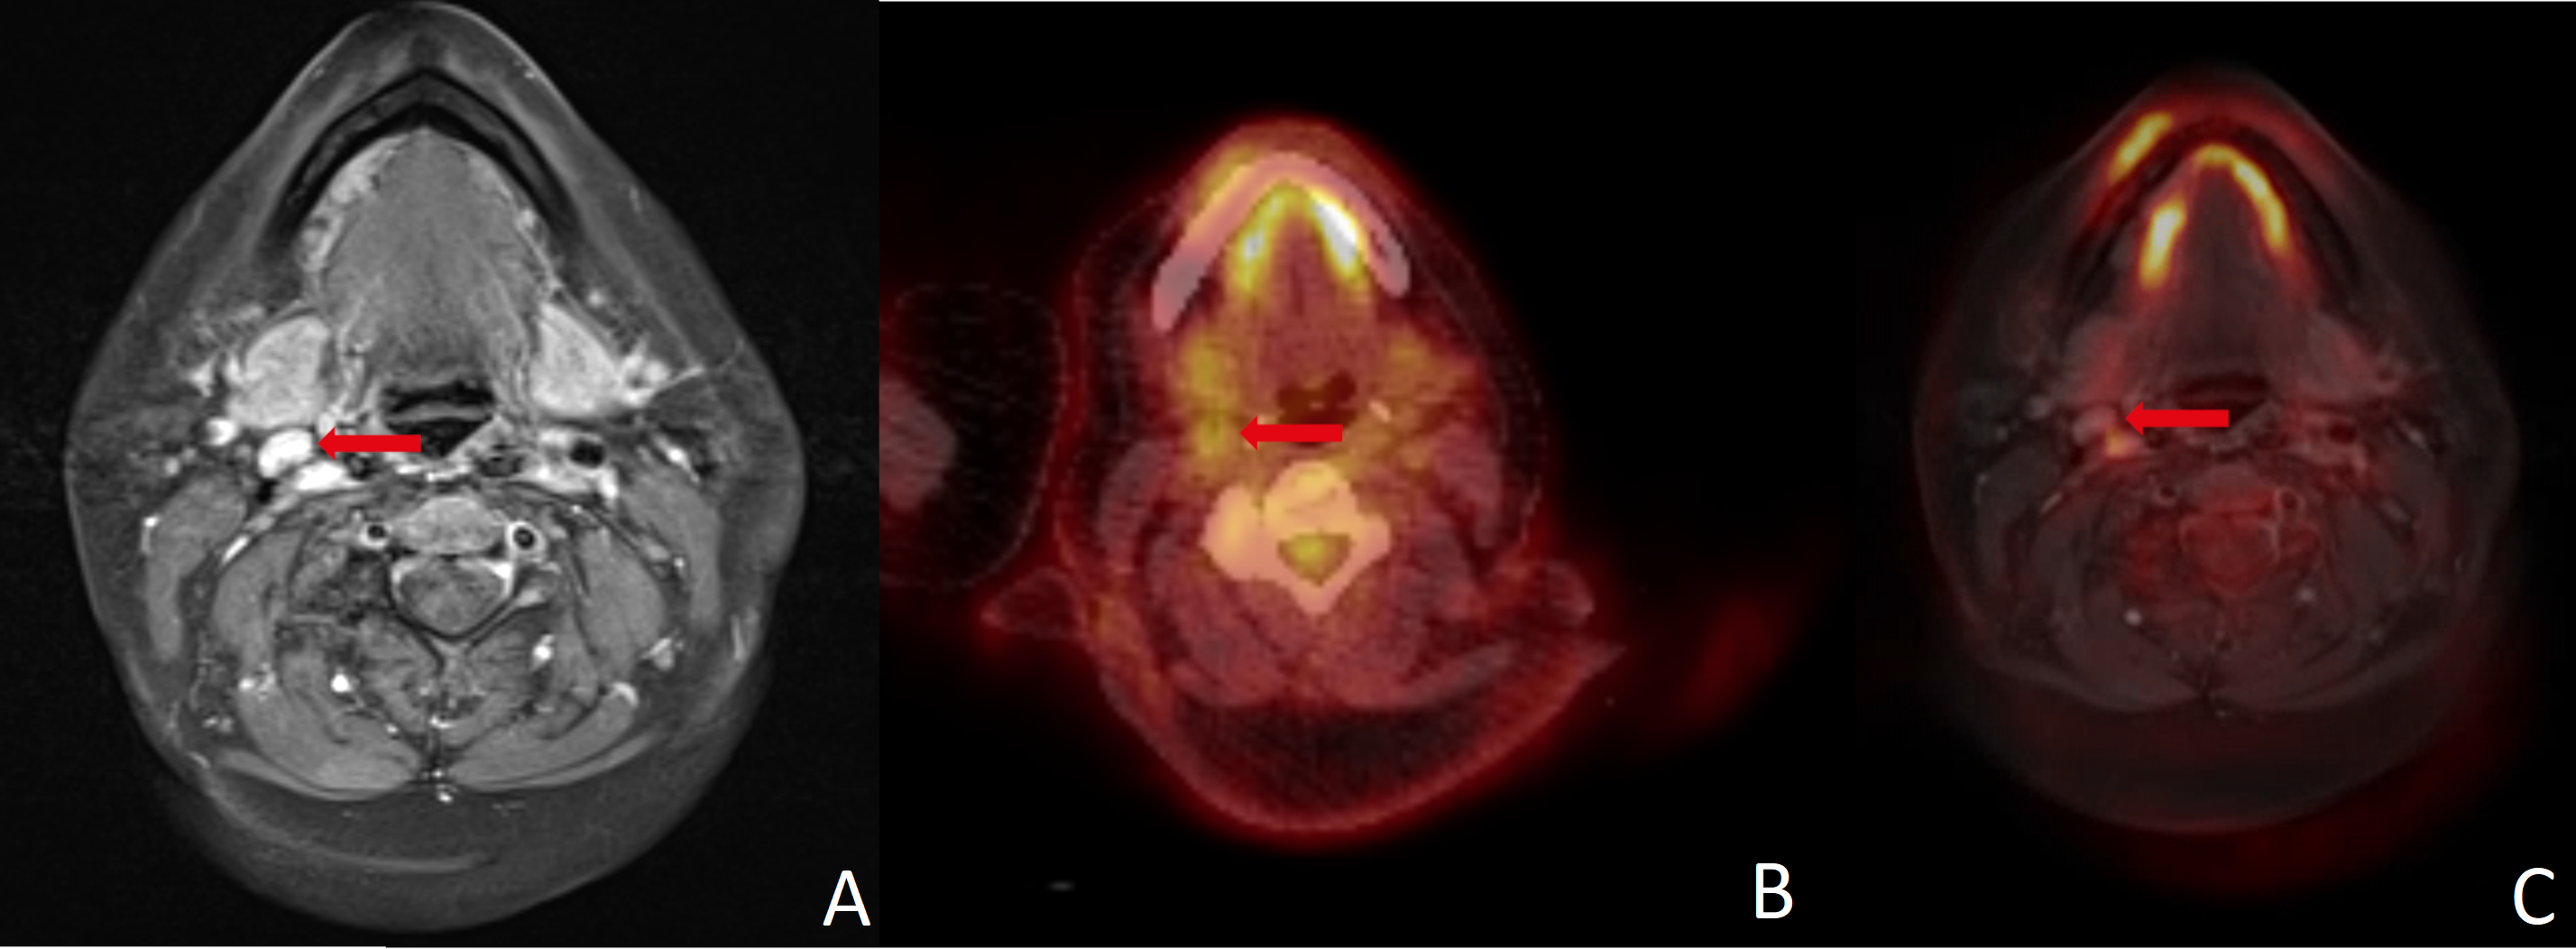

Figure 3.

(A) Size and contrast enhancement in MRI were misleading in this histopathologically negative neck. Absence of FDG uptake led to correct negative results in (B) PET/CT and (C) PET/MRI. A combination of different modalities, image fusion in particular, can improve the assessment of cervical lymph nodes. Red arrows point to the region of interest in all three imaging modalities.

MRI indicated LNM in two (5.4%) histologically negative patients. PET/CT was false positive in one (2.7%) patient and PET/MR did not depict any false positive neck findings (see Figure 3). In seven (18.9%) patients with divergent results between imaging methods, one did not show an elevated risk of LNM in histology.

Both MRI and FDG-PET/CT have proven to have good diagnostic accuracy for detecting LNM in HNC in previous investigations [6,17,26,27,28,29]. Studies investigating the simultaneous use of MRI and PET have shown promising results in terms of diagnostic accuracy for detecting cervical LNMs [5,6,30,31]. To determine the clinical value of PET/MRI fusion, we compared the results of MRI, PET/CT and PET/MRI in patients with HNC. All patients received MRI and PET/CT on the same day and surgery afterwards. Histopathological results served as the gold standard. MR images and PET data were merged retrospectively for research purposes only. To the best of our knowledge, this study is the first to investigate the diagnostic accuracy of retrospectively fused PET/MRI in a cohort of this size at a single center. The results are consistent with existing data regarding the diagnostic accuracy of MRI and PET/CT. From a clinical perspective, a reduction in false negative results is particularly desirable [6]. Unfortunately, data from the present investigation did not demonstrate evidence in this direction for any of the examined modalities. Although PET/MRI did not show any false positive results in our data, false negatives were as high as in MRI and PET/CT. In our cohort, at least one modality showed a false negative result in seven (18.9%) patients. In this context, a combination of modalities could be beneficial as there were only two (5.4%) patients where all modalities showed a false negative result. However, we do not suggest omitting neck dissection based solely on imaging findings. Nonetheless, in selected cases with high intraoperative risk, a combination of different imaging modalities is favorable for guiding therapeutic decisions (see Figure 3).